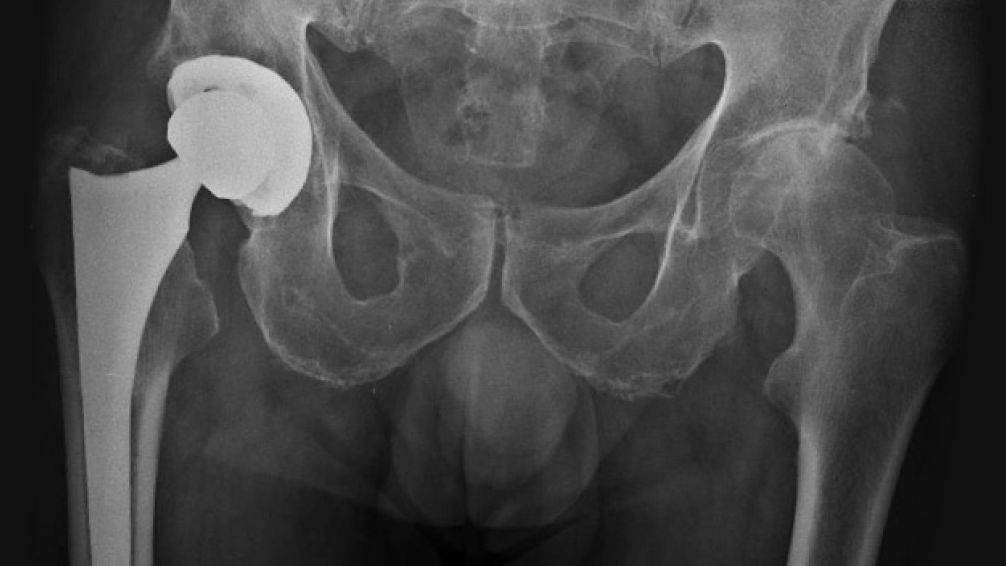

La atención médica y quirúrgica en Tandil enfrenta dificultades relacionadas con IOMA, particularmente en el área de traumatología y ortopedia. Profesionales del sector aseguran que pacientes con cirugías programadas para reemplazos de cadera se ven afectados por retrasos en la entrega de prótesis, pese a tener autorizaciones de la cirugía, internación y anestesia.

Esto afecta principalmente a prótesis de cadera, cuyo costo puede oscilar entre 3.000 y 5.000 dólares, según sean nacionales o importadas.

El médico destacó en Radio Tandil que cualquier cirugía de ortopedia requiere cuatro factores alineados: autorización de la cirugía, internación, anestesia y disponibilidad del implante. Los retrasos generan reprogramaciones constantes, estrés para los pacientes y dificultades organizativas para los equipos médicos, que deben coordinar quirófanos, anestesistas y proveedores de prótesis.

Los profesionales esperan que IOMA regularice los pagos de manera inmediata, garantizando así la atención quirúrgica programada y evitando complicaciones para los pacientes que requieren reemplazos de cadera.